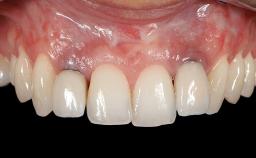

Adequate peri-implant soft-tissue thickness is essential not only for esthetic but also for functional reasons. In this case, Vincenzo Iorio Siciliano demonstrates how he achieved increased height and thickness of posterior peri-implant soft tissues to obtain a stable mucosal seal and a width of keratinized tissue favorable to toothbrushing.

The patient, a healthy 38-year-old woman, was referred for increasing the width of the keratinized tissues at the buccal aspect of dental implant 46. The site exhibited a premature-closure screw exposure caused by trauma during chewing, with inadequate keratinized tissue.